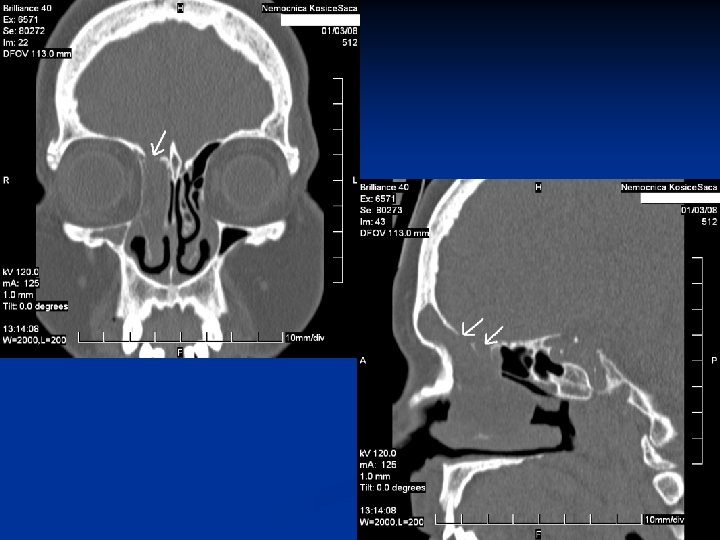

Kazuistika č. 1 n n n 67 ročná pacientka Infekt HCD v 02/2015, odvtedy výtok čírej tekutiny z pr. nosnej dierky, bolesť hlavy 29. 7. 2015 prvé vyš. na našej ORL amb. Vyš. β 2 TRF – potvrdenie likvoru CT PND Suponovaná idiopatická rinolikvorea vpravo, indik. FESS operácia na 21. 9. 2015

Kazuistika 2. n n n 48 ročný pacient Obojstranná FESS operácia v CA pre nosovú polypózu Predoperačne lokálne a celkovo kortikoidy 2. pooperačný deň udáva výtok čírej tekutiny z pravej nosovej dierky Na základe anamnézy, endoskopického vyš. a HRCT diagnostikovaná iatrogénne spôsobená rinolikvorea vpravo v oblasti lamela lateralis, indikovaná duraplastika vpravo

Kazuistika 3. n n n 61 - ročná pacientka FESS operácia vpravo pre nosovú polypózu s postihnutím pravej maxilárnej, čelovej dutiny a predných ethmoidov Peroperačne odstránený zo stredného nosového priechodu cystický polypózny útvar, dutiny vyplnené hlienohnisom Pacientka týždeň po operácii pri amb. kontrole udáva výtok čírej tekutiny z pravej nos. dierky Na základe anamnézy, endoskopického nálezu a HRCT diag. rinolikvorea v oblasti nazofrontálneho vývodu a stropu ethmoidov, indikovaná duraplastika vpravo Stav hodnotíme ako meningokélu s následnou rinolikvoreou